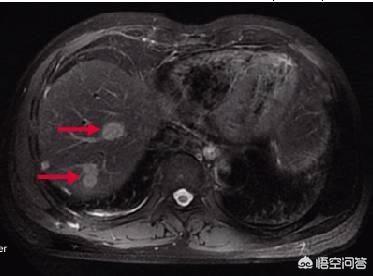

Die Inzidenz von Lebermetastasen bei Dickdarmkrebs ist hoch, etwa 50-70 Prozent, und einige werden nach der Operation oder vielleicht schon vorher entdeckt. Es ist nicht ungewöhnlich, dass kleine Primärherde und viele, große Metastasen auftreten.

Tumordurchmesser ist sehr klein, in der Regel 1-2mm, die Metastasen haben kann, wenn der Tumor ist sehr klein, ohne Lebermetastasen, mit TNM-Staging ist wahrscheinlich ein Stadium I Patienten, einfache Operation kann mehr als 90% der 5-Jahres-Überlebensrate, eine vollständige Heilung ist sehr wahrscheinlich, aber wenn Lebermetastasen auftritt, wird die Situation schlecht.

Lebermetastasen bei Dickdarmkrebs sind sehr häufig, und Dickdarmkrebspatienten müssen zunächst eine Bauch-CT und eine Brust-CT durchführen lassen, um festzustellen, ob es Leber- und Lungenmetastasen gibt. Durch die hämatogene Metastasierung folgt der Darmkrebs nicht nur der Lokalisation, sondern auch dem Blutkreislauf, die Krebszellen werden abgestoßen und gelangen über den Blutkreislauf in die Leber, wo sie Metastasen bilden, die eine sehr häufige Metastasierung von Darmkrebs darstellen. Sobald eine Lebermetastase auftritt, handelt es sich um ein fortgeschrittenes Stadium, und eine Lebermetastase ist nicht völlig unbehandelbar. Wenn es sich um oligometastatische Lebermetastasen handelt, die Zahl der Metastasen relativ gering und die Lage relativ gut ist, können sie durch eine gleichzeitige Resektion von Dickdarm und Leber beseitigt werden; wenn die Metastasen relativ groß sind, müssen sie durch eine systemische Chemotherapie bekämpft werden.